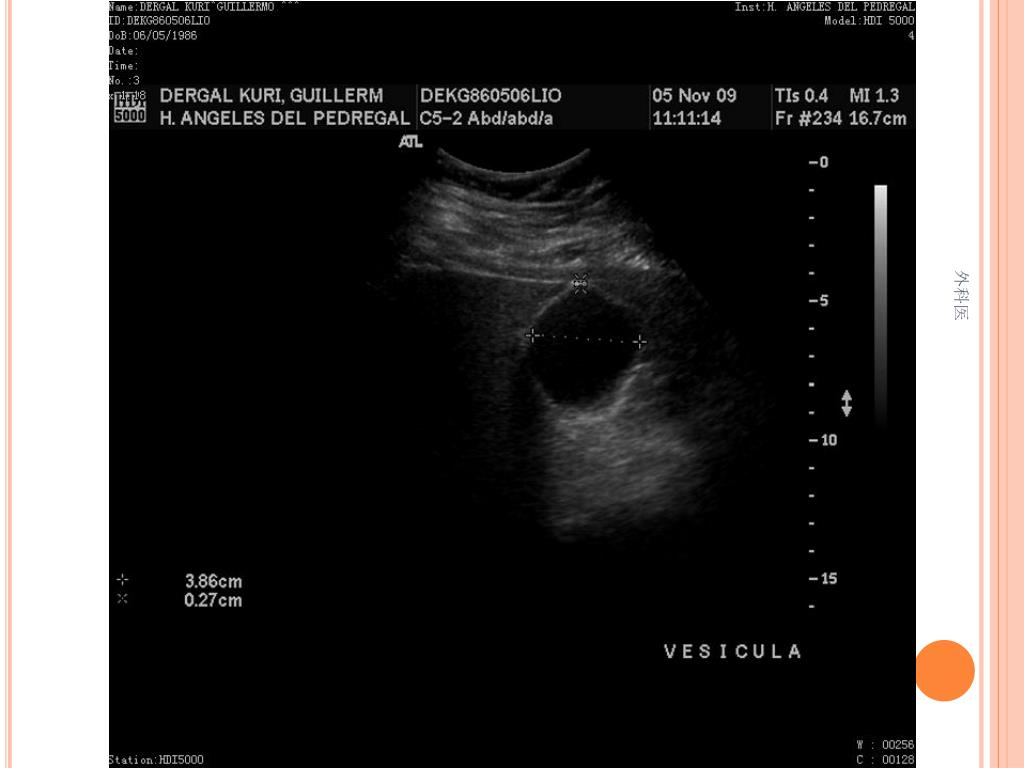

44. Tips • Leucocitos Mas de 20000/ml • Mas de 20% de la apéndices no se llenan con el bario por enema. • USG sensibilidad del 85% y Especificidad de mas 90% para Apendicitis Aguda. • TAC de Abdomen cortes de 5mm, sensibilidad y especificidad del 90% para dolor abdominal. • Analisis de 75000, taza de apendice negativa de 6% Hombres y 13% Mujeres 外科医